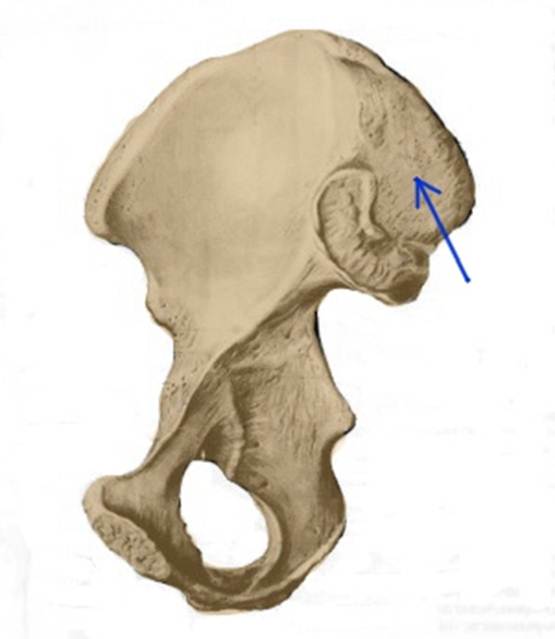

S:Стрелка указывает на spina iliaca posterior superior

S:Стрелка указывает на lambium internum

S: Стрелка указывает на spina iliaca posterior inferior

S: Стрелка указывает на tuber ischiadicum (латинский язык).

S: Стрелка указывает на incisura ischiadica minor

S: Стрелка указывает на incisura ischiadica major

S: Стрелка указывает на facies auricularis

S: Стрелка указывает на facies sacropelvica

S: Стрелка указывает на eminentia iliopubica